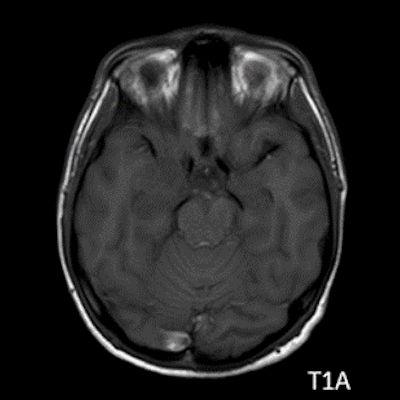

- A) Sağ temporal lob anteromedialinde silik sınırlı BT’de hipodens (ok), MRG’de T2AG ve FLAIR hiperintens (oklar), T1AG izo-hipointens (ok) sinyal özelliğinde ekspansil kitlesel lezyon izlenmektedir.

- MRG: T1A serilerde solid komponent izo-hipointens, T2A serilerde genellikle hiperintens sinyalde görülür. Peritümöral T2/FLAIR hiperintens kitle ödemi oldukça nadirdir. T1 C+ görüntülerde solid komponentte değişken oranda kontrastlanma ,T2*(SWI) serilerde eğer kalsifikasyon eşlik etmekteyse buna bağlı blooming artefaktları görülebilir.